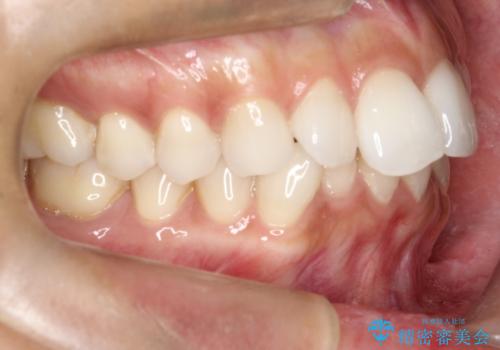

【インビザライン】前歯の凸凹をIPRで改善

- 前歯の凸凹を主訴に来院されました。

前歯を並べるために歯と歯の間にヤスリを入れてわずかに歯を削ることでスペースを確保しています。

歯と歯の間にヤスリを入れてわずかに歯を削ることでスペースを確保する処置をIPRと呼びます。

当院では拡大鏡を用いて丁寧に処置することで歯冠形態を損なわずに行うことができます。